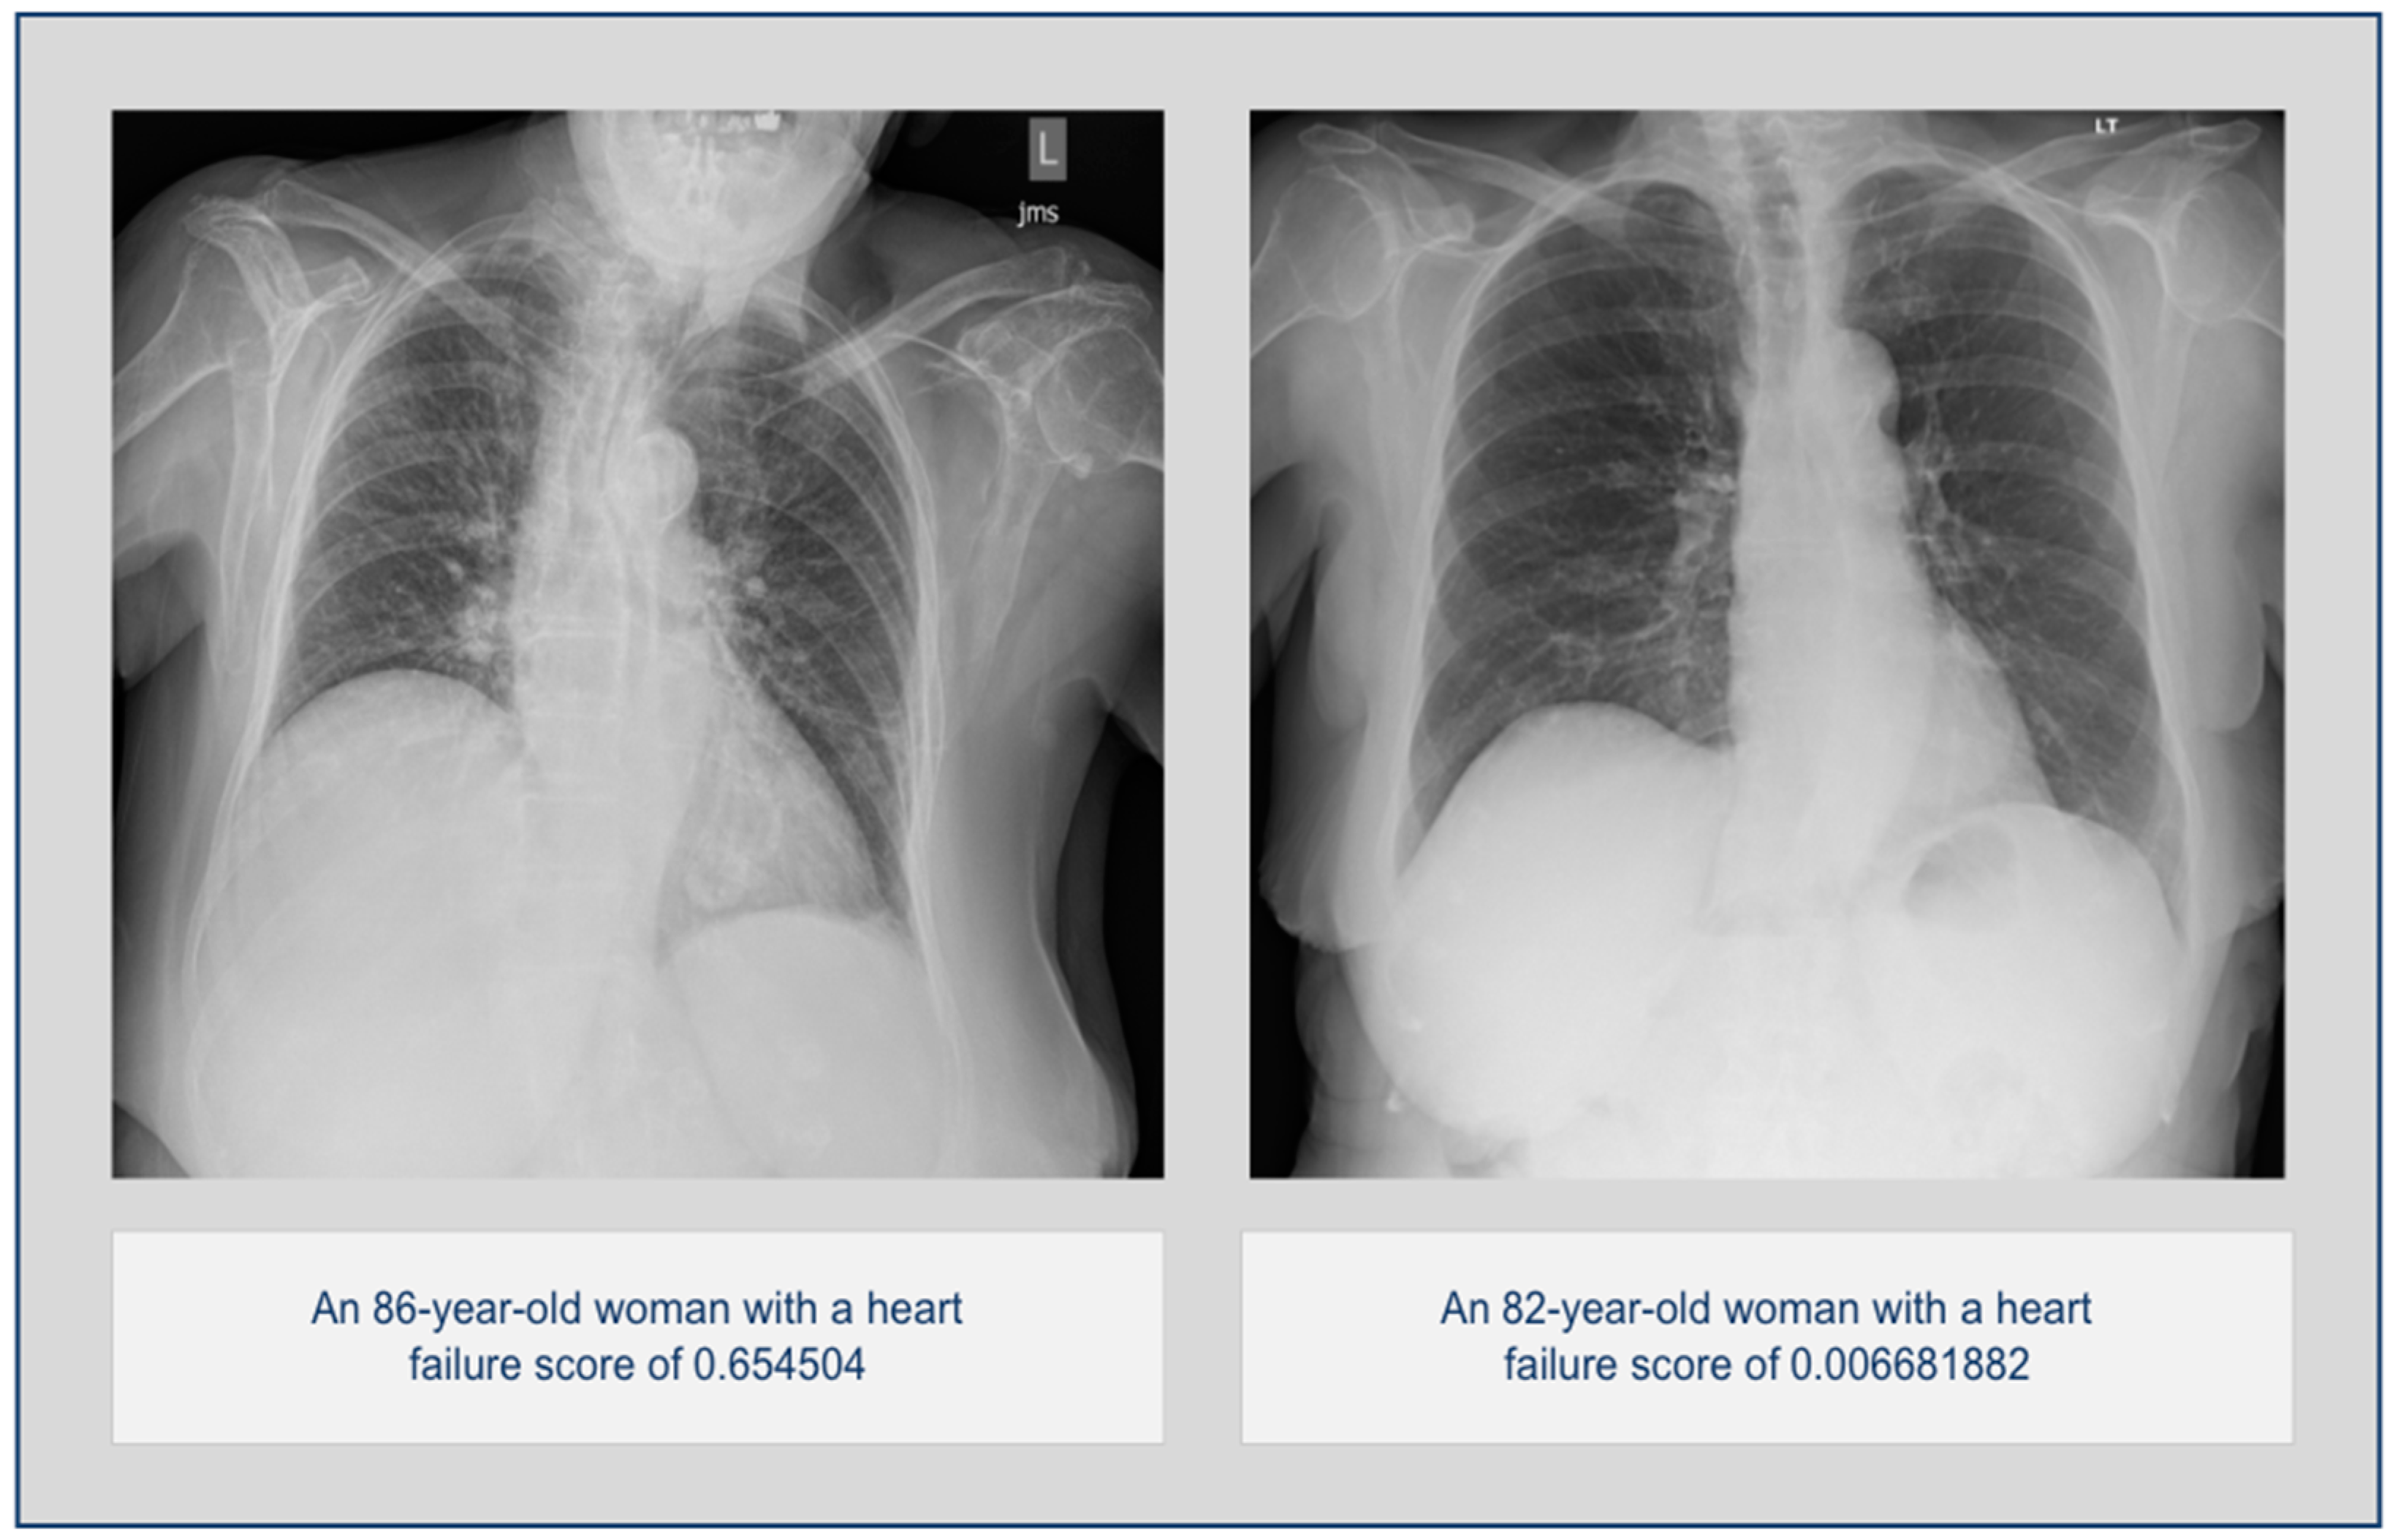

2.3. AI Algorithm

3. Results

3.1. Overall Statistics